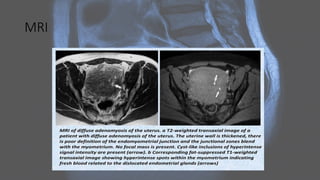

MRI

On MRI • MRIdisplays the zonal anatomy of the uterus. The myometrial layers are indistinguishable on T1 imaging. It can be divided into three zones on T2 weighted imaging7 : • high T2 signal of endometrium • low T2 signal of inner myometrium, known as the junctional zone • intermediate T2 signal of the outer myometrium .